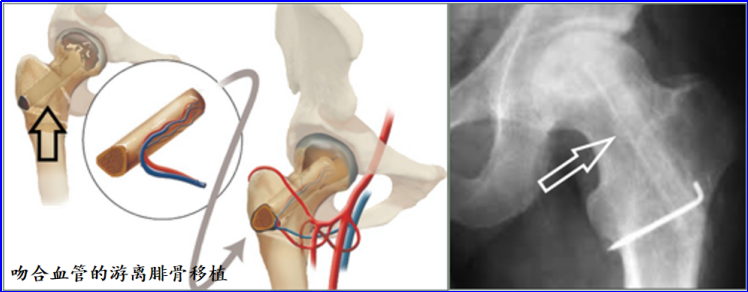

血管化骨移植术

恢复坏死病灶的血液供应对于股骨头坏死(ONFH)的成功治疗至关重要。血管化骨移植术所移植的骨组织具有完整的血液供应和成骨潜能(如带血管蒂髂骨移植、带血管蒂腓骨移植),能够促进坏死区域的骨愈合,并提供有活力的结构性支撑,以防止关节软骨塌陷。

血管化骨移植术通常推荐用于FicatⅠ至Ⅲ期股骨头坏死。与髓芯减压术或非血管化骨移植术相比,血管化骨移植术的影像学进展更慢,塌陷率更低,转为全髋关节置换术的概率也更低。该方法对30岁以下的青少年患者疗效更佳,还可用于治疗严重的骨坏死。

血管化骨移植术需要更复杂的手术操作、更长的手术时间,且对手术人员的要求更高。患者的恢复时间可能会延长,需要3至6个月的保护性负重。其并发症可能包括感染、移植物坏死以及股骨近端骨折风险增加。此外,供区可能出现的并发症(包括拇长屈肌挛缩、腓神经损伤、踝关节不稳和步态改变)的发生率可达13%–20%。